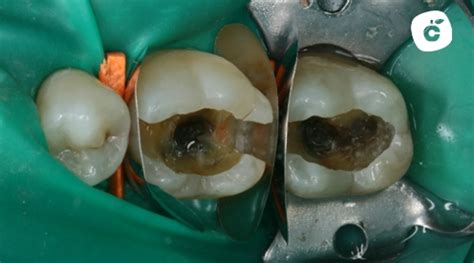

Destacar, en primer lugar, que en un material externo no producen caries pero podemos observar lesiones tanto en el tejido que envuelve la obturación (empaste) presente como en otros puntos del diente. Cuando la nueva lesión de caries se produce alrededor de una obturación ya existente, se denomina “filtración”. Es decir, presencia de filtraciones de bacterias, con la consecuente lesión erosiva, en la unión entre el empaste y el diente.

Esta zona crítica puede ser vulnerable a la acumulación de placa bacteriana y, eventualmente, al desarrollo de caries. Cuando un diente ha sufrido diferentes lesiones de caries y el tejido remanente es escaso, puede ser necesaria la restauración mediante incrustaciones de cerámica, para poder dar a la pieza dental una mayor resistencia y durabilidad.